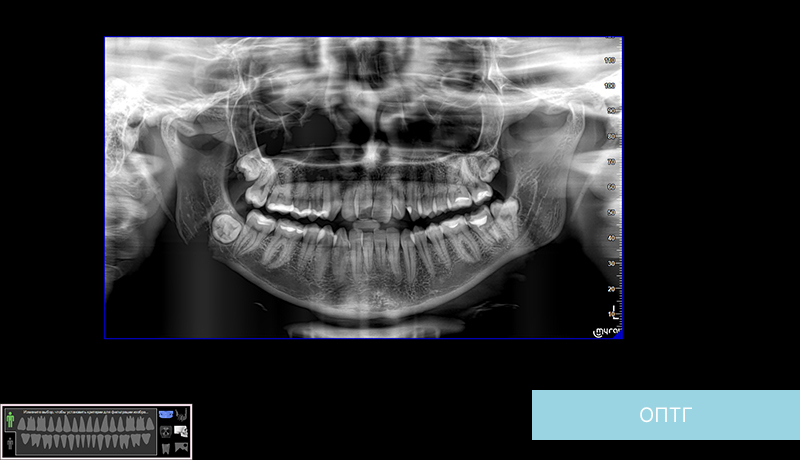

Ортопантомограмма – это как карта сокровищ для стоматолога. Она позволяет увидеть всю картину целиком: зубы‚ кости челюстей‚ височно-нижнечелюстные суставы‚ гайморовы пазухи. Но расшифровка этой карты требует опыта и времени. И вот тут на помощь приходит ИИ. Представьте себе‚ что у вас есть ассистент‚ который мгновенно анализирует снимок‚ выявляет потенциальные проблемы и даже предлагает варианты лечения. Звучит как научная фантастика? Но это уже реальность.

Ортопантомограмма (ОПТГ) – это панорамный рентгеновский снимок‚ который отображает все зубы верхней и нижней челюсти‚ а также окружающие их структуры; Этот снимок позволяет стоматологу получить общее представление о состоянии зубочелюстной системы пациента.

ИИ‚ а точнее‚ алгоритмы машинного обучения‚ обученные на огромном количестве ортопантомограмм‚ способны выявлять мельчайшие детали и закономерности‚ которые могут ускользнуть от человеческого глаза. Эти алгоритмы анализируют изображение пиксель за пикселем‚ выявляя аномалии и признаки различных заболеваний.